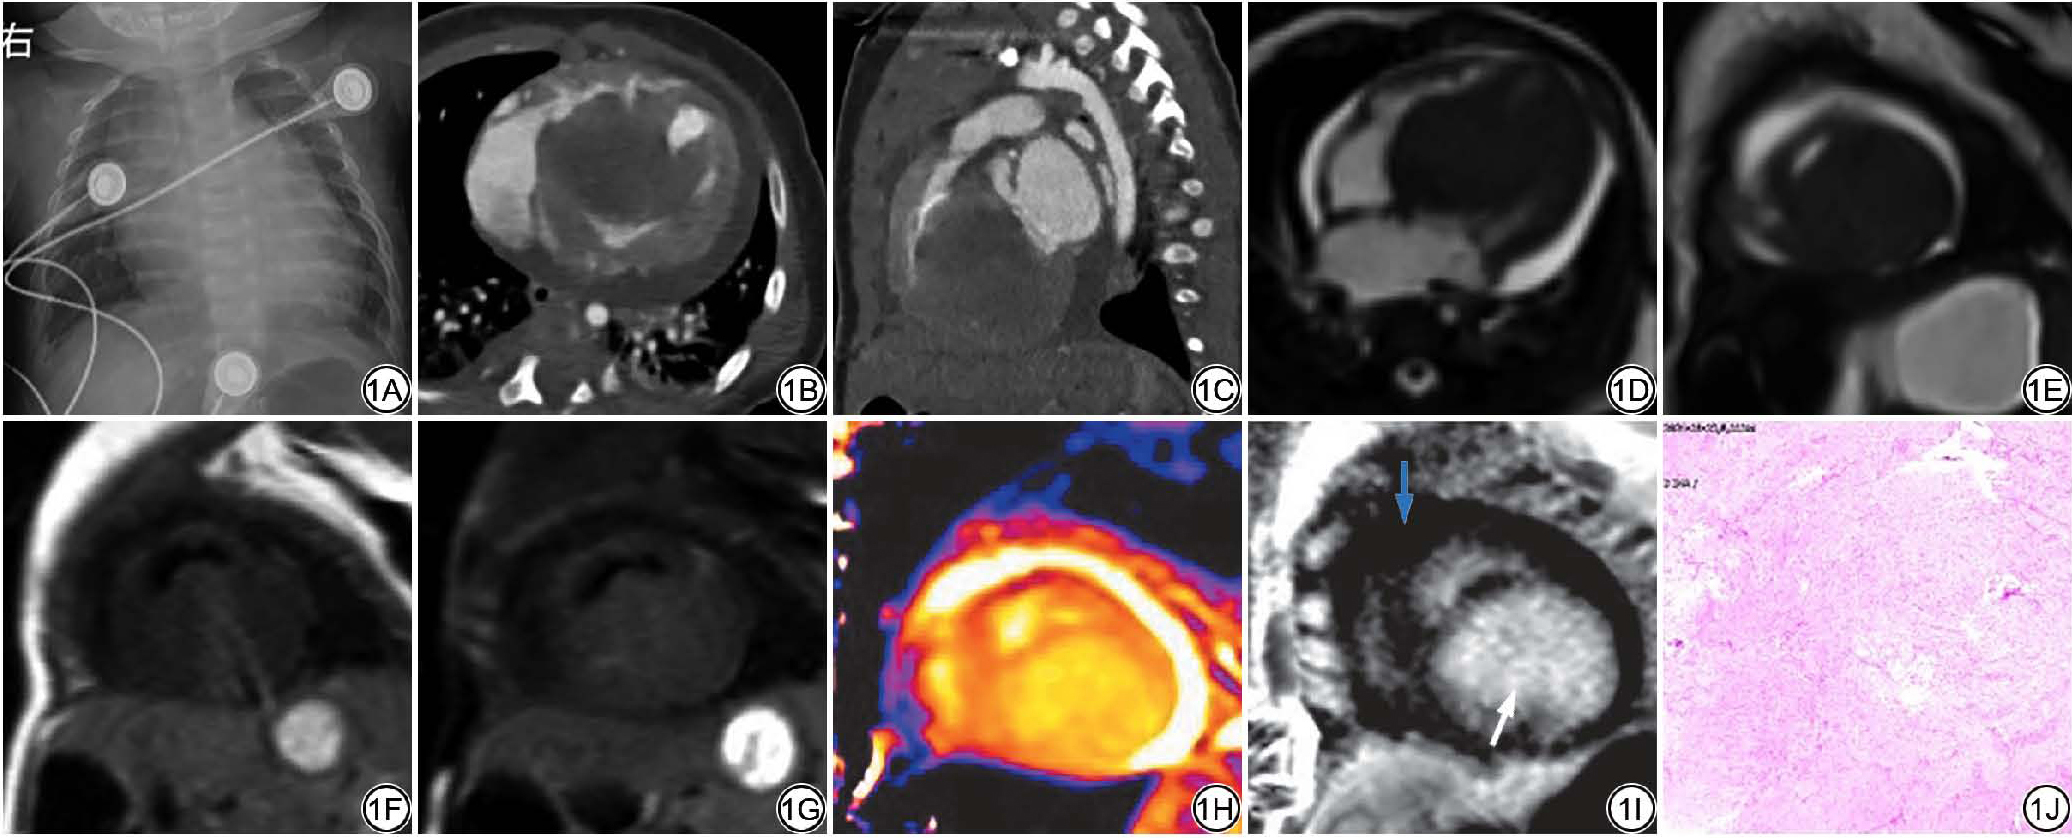

X线胸片提示:心影显著增大(图1A)。超声心动图提示:左室腔内实性占位,基底附着点疑似位于后室间隔上1/2处,远端直达左室侧壁心尖段及心尖部,考虑黏液瘤或脂肪瘤可能;Ⅱ孔型房间隔缺损(中央型)。心脏CT提示:心脏增大,左心室腔内占位,似起源于室间隔及左心室下壁,病变致二尖瓣口、左心室流出道重度狭窄(图1B1C);心脏磁共振(cardiac magnetic resonance, CMR)成像提示:左心室间隔壁及下壁巨大肿块样占位(图1D1E),T1WI呈等信号(图1F),T2WI压脂呈稍高信号(图1G),肿块于收缩期和舒张期大小未见明显变化,肿块突向左心室腔内,大小约25.6 mm×43.9 mm×56.4 mm;左心室腔明显受压、容积明显减小,左心室流出道明显狭窄,左心房扩大。首过灌注示:团块状充盈缺损影;肿块native T1 mapping范围为1703~1717 ms(图1H),T2 mapping范围为68~84 ms。CMR钆对比剂延迟强化示肿块呈中度延迟强化(图1I)。综合影像学特征,符合良性肿瘤性病变的特征,诊断心脏纤维瘤的可能性大。

图1  女,2月龄,左心室心脏纤维瘤。1A:X线胸片示心影显著增大。1B~1C:心脏CT左心室实性占位,基底附着点疑似位于后室间隔上1/2处,远端直达左室侧壁心尖段及心尖部;左心房显著扩大。1D~1E:心脏MRI电影序列四腔心、短轴位示左心房、左心室显著增大,左心室间隔壁及下壁巨大肿块样占位;1F~1G:黑血序列T1WI示肿块呈等信号,脂肪抑制T2WI示肿块呈稍高信号;1H:T1 mapping序列成像示 native T1 mapping值显著延长(1703~1717 ms);1I:延迟增强PSIR(phase-sensitive inversion recovery)序列:显示肿块呈明显均匀延迟强化,未受累室间隔心肌低信号、未见明显异常强化(白箭指病灶,蓝箭指正常心肌)。1J:病理图(HE ×200),显示纤维母细胞、肌纤维母细胞增生性病变,瘤细胞温和,核分裂像不易见。

Fig. 1  Female, 2 months old, left ventricular cardiac fibroma. 1A: The chest X-ray shows a significant enlargement of the cardiac silhouette. 1B to 1C: Cardiac CT shows a solid mass in the left ventricle, with the basal attachment point suspected to be located at the upper half of the posterior interventricular septum, extending distally to the lateral wall of the left ventricle, apical segment, and apex; the left atrium is significantly enlarged. 1D to 1E: Cardiac MRI cine sequences in four-chamber and short-axis views show significant enlargement of the left atrium and left ventricle, with massive tumor-like masses in the left ventricular septum and inferior wall. 1F to 1G: Black-blood sequence T1WI shows the mass with isointense signal; fat-suppressed T2WI shows the mass with slightly hyperintense signal. 1H: T1 mapping sequence imaging shows that the native T1 mapping values are significantly prolonged (1703 to 1717 ms); 1I: Delayed enhancement PSIR sequence: The mass shows obvious homogeneous delayed enhancement, the interventricular septal myocardium is not involved and displays low signal, and no significant abnormal enhancement is observed (The white arrow indicates the lesion, and the blue arrow indicates normal myocardium). 1J: Pathological image (HE ×200) showing proliferative lesions of fibroblasts and myofibroblasts. The tumor cells are mild, and mitotic figures are not easily observed.